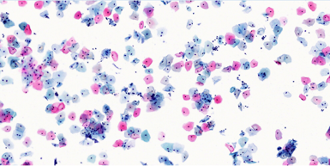

Bilder von links nach rechts: Dünnschichtzytologie (ThinPrep Pap-Test), Einzelschnitt-Histologie (Magen, H&E)

Dünnschichtzytologie (ThinPrep Pap-Test)